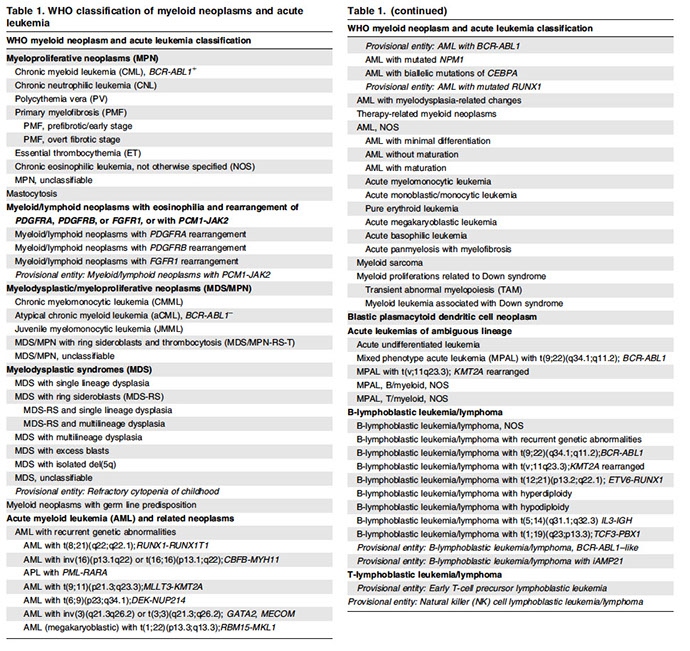

Myeloid Neoplasms

Myeloproliferative Neoplasms

Chronic myeloid leukemia (CML), BCR-ABL1-positive

Chronic Neutrophilic Leukemia (CNL)

Polycythemia vera (PV)

Primary Myelofibrosis (PMF)

- Prefibrotic / early PMF

- Overt fibrotic myelofibrosis

Essential Thrombocythemia (ET)

Eosinophilia overview *** BONO***

Chronic Eosinophilic Leukemia (CEL), NOS

Myeloproliferative Neoplasms, Unclassifiable

Mastocytosis (not considered an MPN)

- Cutaneous mastocytosis

- Systemic mastocytosis

- Mast cell sarcoma

Myelodysplasic / myeloproliferative neoplasms

Chronic MyeloMonocytic Leukemia (CMML)

Atypical Chronic Myeloid Leukemia (aCML)- BCR-abl1 negative

MDS /MPN with ring sideroblasts and thrombocytosis ( MDS /MPN–RS-T)

Myelodysplastic / Myeloproliferative neoplasm - unclassifiable

Myelodysplastic Syndromes

Acute myeloid leukemia (AML) and related precursor neoplasms

Myeloid / lymphoid neoplasms with eosinophilia and gene rearrangement

Blastic plasmacytoid dendritic cell neoplasm

Myeloid neoplasms with germline predisposition

Acute leukemias of ambiguous lineage

Acute undifferentiated leukaemia

Mixed-phenotype acute leukaemia with t(9;22)(q34.1 ;q11.2); BCR-ABL1

Mixed-phenotype acute leukaemia with t(v; 11 q23.3); KMT2A-rearranged

Mixed-phenotype acute leukaemia, B/myeloid, NOS

Mixed-phenotype acute leukaemia, T/myeloid, NOS

Mixed-phenotype acute leukaemia, NOS, rare types

Acute leukaemias of ambiguous lineage, NOS